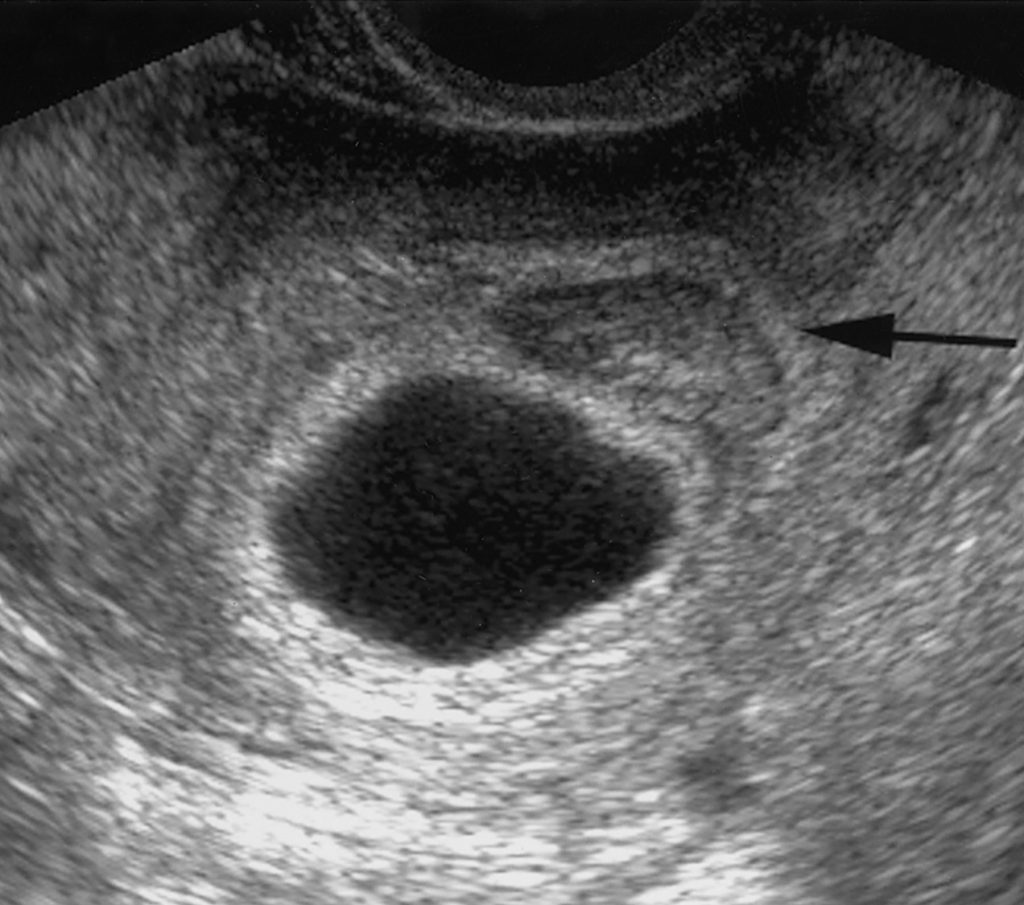

Hanya Nampak Kantung Saja Dr Zubaidi Hj Ahmad Menulis

Kantung Bayi Punca Dan Tanda Tanda Kehamilan Kosong Wajib Tahu

Penyebab Kantung Janin Belum Terlihat Walaupun Ujian Kehamilan Positif